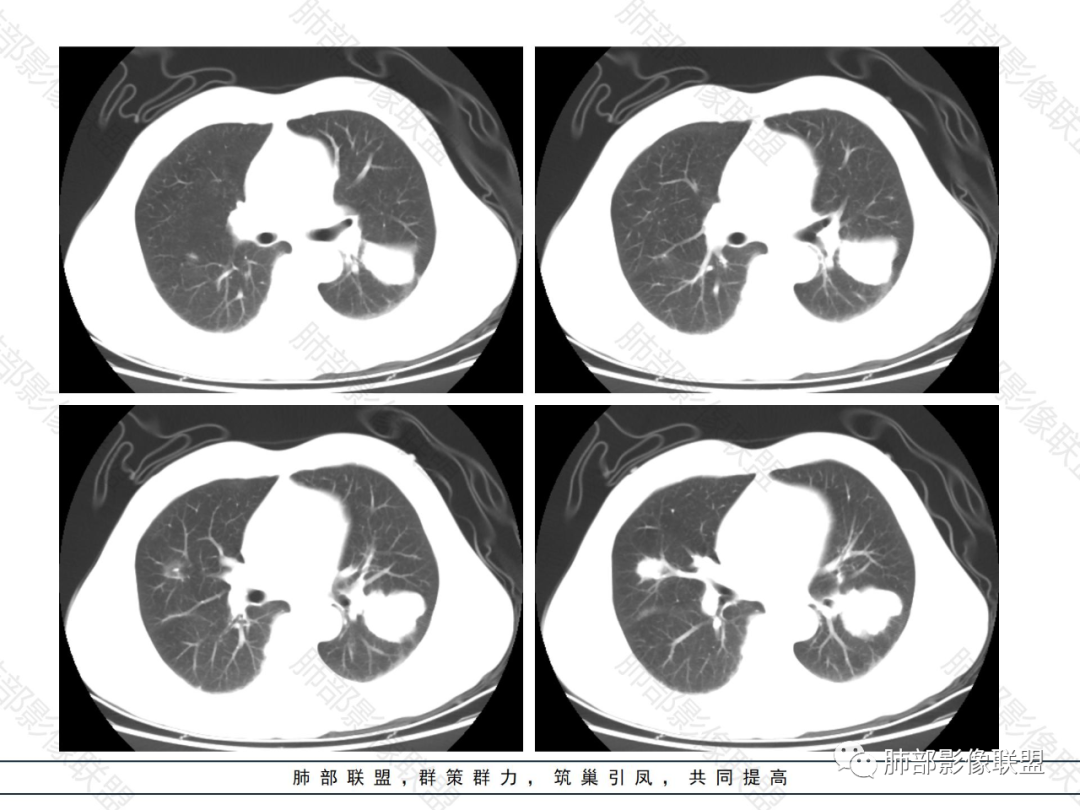

双肺多发大小不等结节,以胸膜下为主,部分边缘平直,彭隆,整体较密实,临床无症状体检发现,考虑淋巴瘤,转移瘤,IMT.

老年男性,发现占位半年,双肺多发结节,病灶边界清晰,浅分叶,部分支气管进入后堵塞,部分病灶内部密实,无增强,考虑真菌感染,淋巴瘤待排除。

双肺多发结节肿块,部分位于胸膜下,部分结节内可见扩张支气管,右肺上叶近肺门处结节呈分叶毛刺,支气管阻塞、扭曲扩张,考虑1淋巴瘤2腺癌转移。

双肺多发结节,密度均匀,部分可见支气管进去后堵塞,有胃部手术史,考虑淋巴瘤?鉴别腺癌转移,其他?

脾大表现,两肺叶多发结节,部分呈肿块(浅分叶轮廊),实性密度,边缘清楚,有膨隆,近胸膜下分布,支气管僵直略扩张,一元论,首选淋巴瘤。

双肺多发结节肿块,胸膜下支气管树旁为主,部分内可见支气管穿行,支气管扩张。淋巴瘤?肉芽肿性多血管炎?鉴别转移

必有路:老年男性,两肺多发结节,团块,病灶都位于胸膜下,血管相关,有支气管充气征,分叶,无坏死,周围无晕疾病谱:隐球菌病,GPA,OP,malt,转移,IgG4相关,栓塞诊断:鉴于患者体检发现半年,症状逍遥重点考虑 淋巴瘤 可能鉴别:隐球菌病,GPA,IgG4相关,转移

多发团块影,胸膜下为主,边缘清楚、膨隆、平直,部分病灶可见分叶,病灶内支气管穿行,血管穿行,考虑淋巴瘤。

刚看了视频,老年男性,体检发现,30年前有胃部手术史。双肺野多发结节肿块影,沿支气管血管束或胸膜下分布,有的结节内似有小空洞,支气管进入走形自然,肿块边缘膨隆,有分叶,支气管进入后有的截断,大部分支气管穿过,走形自然,纵隔内未见明显肿大淋巴结,总体考虑淋巴瘤,炎性肉芽肿(肉芽肿血管炎或隐球菌肺炎)等。考虑后者可能性大,肉芽肿血管炎或隐球菌肺炎,鉴别淋巴瘤。

病变分布特点,胸膜下,叶间胸膜下为主,呈大小不等结节级团块影,部分病灶内见支气管影,病灶收缩不明显,从分布及慢性发病看,隐球和淋巴瘤都可,补充增强,病灶内见血管穿行,强化不明显,支持淋巴瘤

老年男性,两肺多发结节肿块,胸膜下分布为主,部分支气管进入闭塞,增强扫描有强化,血管穿行无破坏,边缘尚光滑,周围无晕,病灶整体膨隆为主,半年病程,症状逍遥,首先考虑淋巴瘤

棉花糖:双肺多大小不等结节,边缘清楚,无毛刺,浅分叶,胸膜下分布为主,内可见支气管穿行,增强后中等程度强化,病灶内血管走行自然,考虑淋巴瘤,鉴别GPA